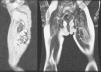

En la RM la masa está contenida en el bíceps crural izquierdo, sin afectación ósea asociada (Figura 2). Internamente se apreciaban áreas irregulares de vacío de señal (Figura 3) (hipointensas en todas las secuencias), secundarias a la presencia de calcificaciones (flechas).

Figura 2.